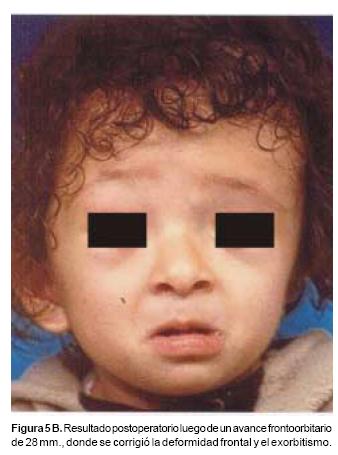

También los controles radiológicos durante el proceso de distracción mostraron que no se produjo la creación de espacios muertos intracraneanos durante los avances. En todos los pacientes con sinostosis bicoronal el avance frontoorbitario produjo excelentes resultados estéticos dando una nueva forma a la región frontal y proyectando mejor el reborde supraorbitario. En los niños con enfermedad de Crouzon y síndrome de Apert, se corrigió en forma muy satisfactoria el exorbitismo al resolver las graves exposiciones corneales (Figuras 5 A, B, C, D, E, F, G, H), en los que se utilizó el avance simultáneo del tercio medio, este cambio óseo corrigió muy satisfactoriamente la retrusión del mismo, ampliando la vía aérea y resolviendo en muchos casos grandes problemas ventilatorios durante el sueño (Figuras 6 A, B, C, D, E, F). Los pacientes con plagiocefalia corrigieron significativamente la deformidad frontoorbitaria y los tejidos blandos suprayacentes se adaptaron a la nueva estructura ósea. La clásica órbita de arlequín de estos niños producida por la sinostosis del frontal con el esfenoides, inmediatamente se ve corregida en su forma y su configuración se hace muy similar con la órbita contralateral (Figura 7)(Fig. 7a, 7b, 7c, 7d, 7e, 7f, 7g) (Cuadro II).